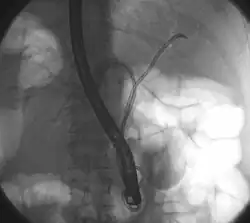

![]() Tumor de Klatskin durante ERCP. El paciente yace sobre su estómago de manera oblicua, por tanto el lado izquierdo de la imagen corresponde al lado izquierdo del paciente. A la izquierda y derecha del sistema biliar se coloca un cable que es necesario para las posteriores inserciones de stents para drenar la bilis. | ||